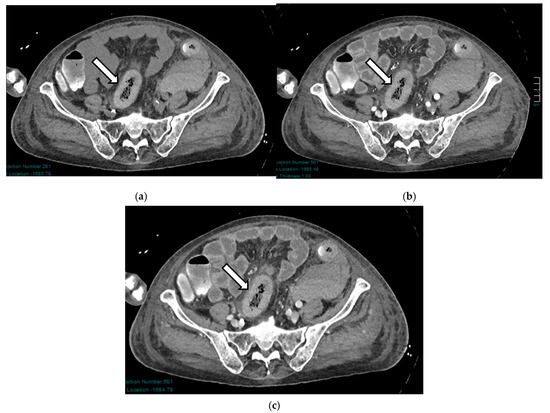

Acute mesenteric ischemia (AMI) is a clinical condition caused by vascular insufficiency, resulting in intestinal damage. Is often underestimated, if not driven by clinical suspicion, due to the non-specific clinical symptoms (usually represented by acute abdominal pain) and the absence of reliable markers, which results in a poor prognosis and high mortality. We can identify three main forms of AMI: arterial, venous, and non-occlusive. Arterial AMI is the most frequent form, caused by occlusion of the superior mesenteric artery or one of its branches. Venous AMI is the least frequent, caused by thrombosis of the superior mesenteric vein or its branches. Non-occlusive AMI is due to a state of hypovolemia, which is frequent in patients who have undergone surgery. Given the difficulty of diagnosis based on the clinic alone, the radiologist plays a central role in identifying radiological signs of intestinal ischemia and in avoiding misdiagnosis. The radiologist’s role is mainly to identify factors predictive of necrosis, which allow us to stratify patients and direct them towards the proper management. The aim of this review is to provide indications for an adequate CT protocol, including an unenhanced phase, an arterial phase, and a venous phase, as well as to underline the features to investigate in the different forms of AMI, in order to increase the diagnostic capacity in this challenging disease. Full article

Show Figures

Figure 1